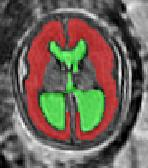

Limiting failures of machine learning systems is of paramount importance for safety-critical applications. In order to improve the robustness of machine learning systems, Distributionally Robust Optimization (DRO) has been proposed as a generalization of Empirical Risk Minimization (ERM). However, its use in deep learning has been severely restricted due to the relative inefficiency of the optimizers available for DRO in comparison to the wide-spread variants of Stochastic Gradient Descent (SGD) optimizers for ERM. We propose SGD with hardness weighted sampling, a principled and efficient optimization method for DRO in machine learning that is particularly suited in the context of deep learning. Similar to a hard example mining strategy in practice, the proposed algorithm is straightforward to implement and computationally as efficient as SGD-based optimizers used for deep learning, requiring minimal overhead computation. In contrast to typical ad hoc hard mining approaches, we prove the convergence of our DRO algorithm for over-parameterized deep learning networks with ReLU activation and a finite number of layers and parameters. Our experiments on fetal brain 3D MRI segmentation and brain tumor segmentation in MRI demonstrate the feasibility and the usefulness of our approach. Using our hardness weighted sampling for training a state-of-the-art deep learning pipeline leads to improved robustness to anatomical variabilities in automatic fetal brain 3D MRI segmentation using deep learning and to improved robustness to the image protocol variations in brain tumor segmentation. Our code is available at https://github.com/LucasFidon/HardnessWeightedSampler.